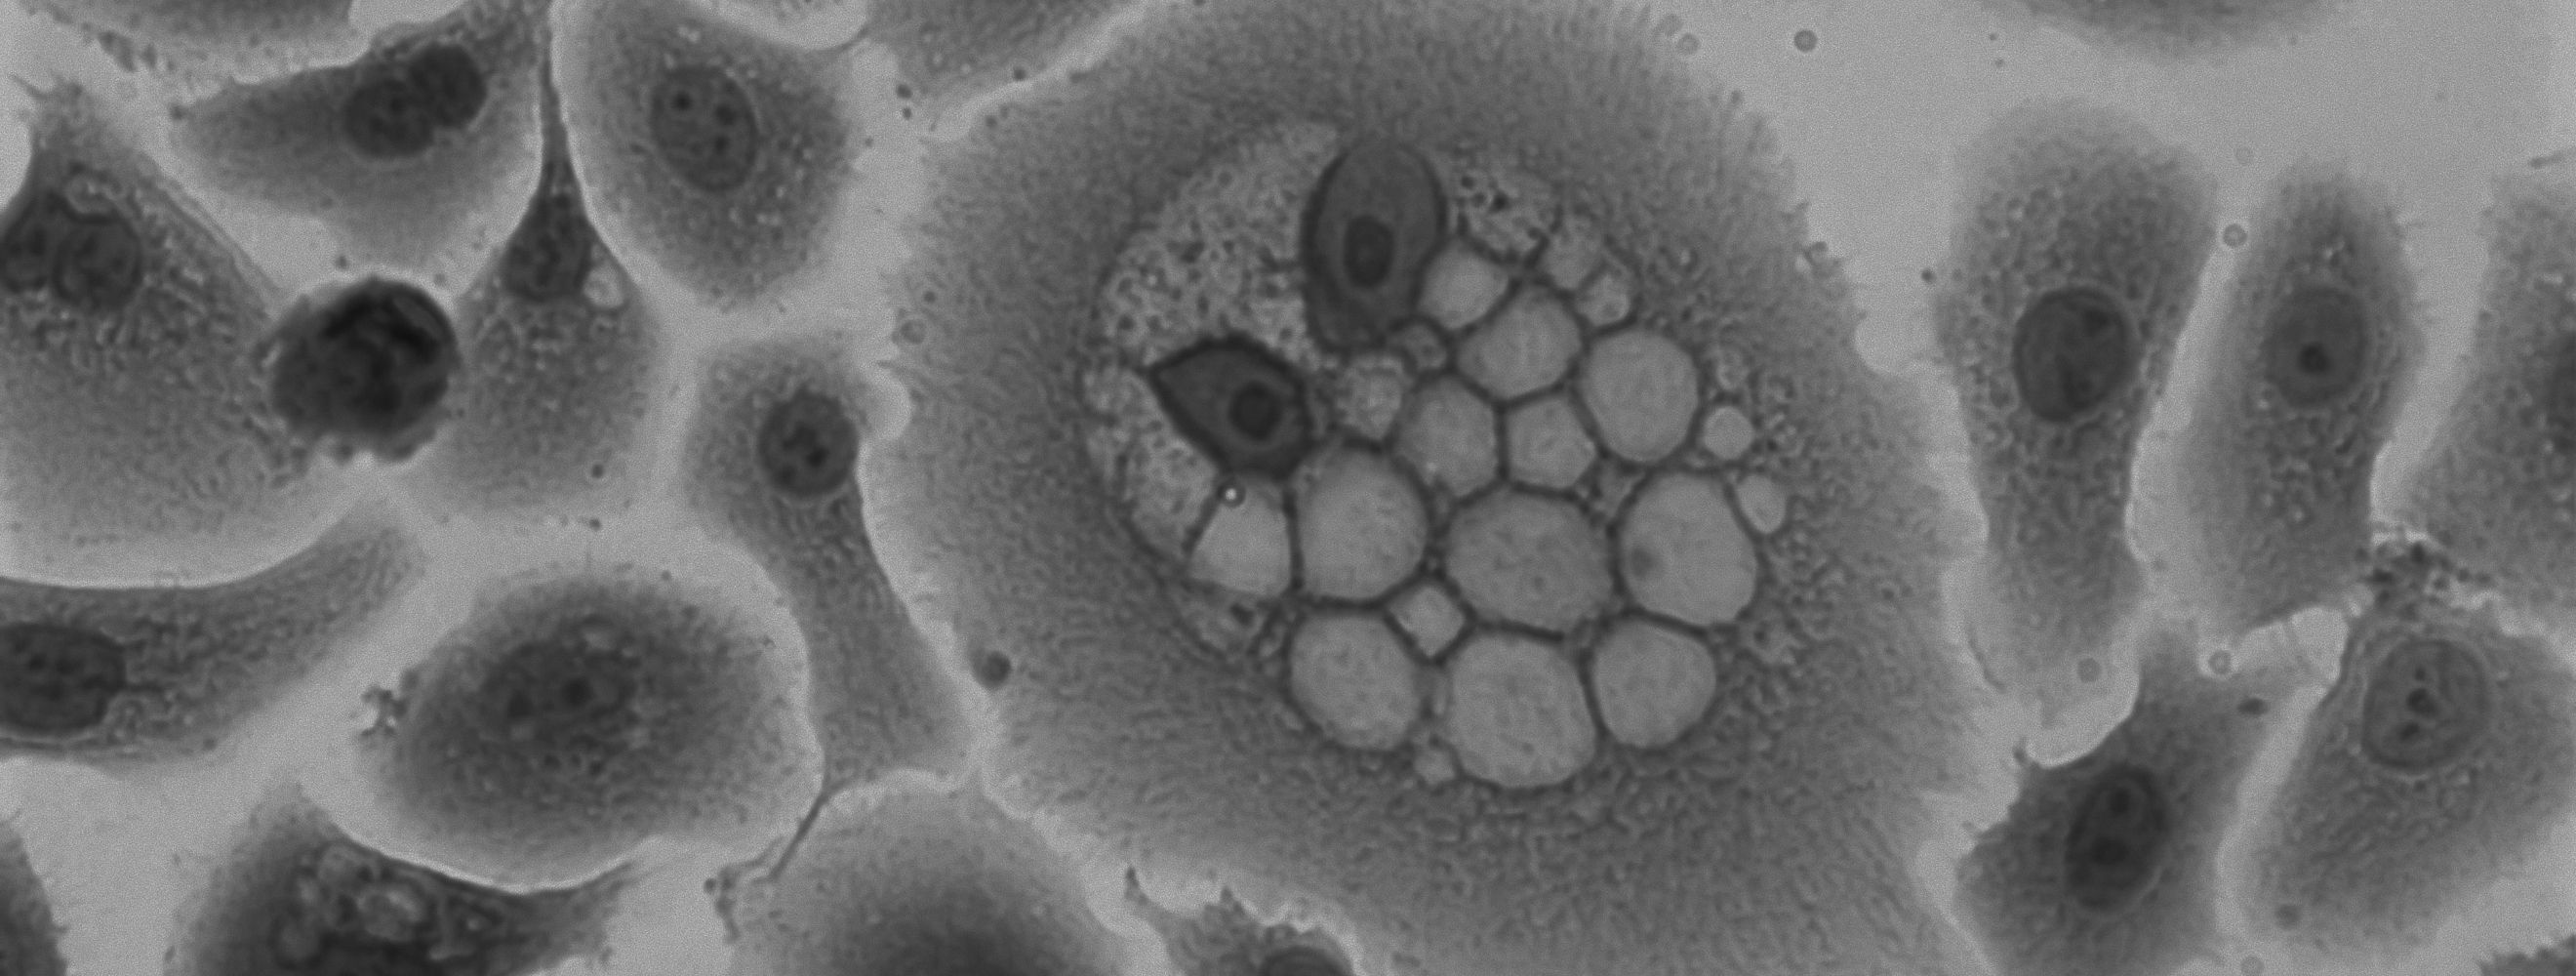

The team built a deep learning AI system that they trained to read routine chest CT scans and provide a thymic health score. This score quantifies how much functional tissue remains versus its fatty replacement. They applied this to 27,612 people from two large cohorts: the National Lung Screening Trial (25,031 people, 12-year follow-up) and the Framingham Heart Study (2,581 people).